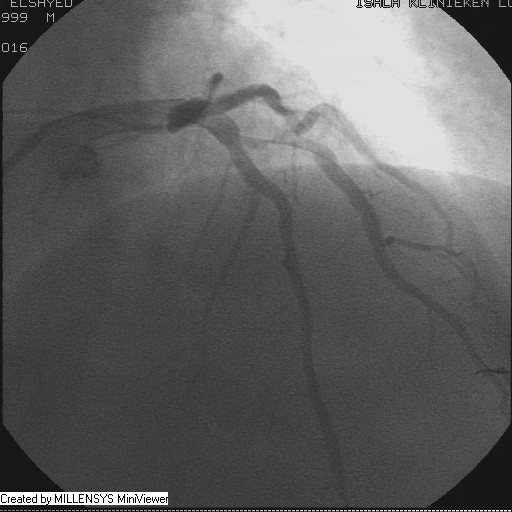

Patient transfered to Cardiac Catheterization Laboratory, coronary angiography showed atherosclerotic coronaries but without significant lesions, especially LAD that was patent with TIMI 3 flow (Figure 1- 5). Re-evaluation of the Angiography showed a small stump that can be for an occluded 1st diagonal (Figure 2a), at that level the LAD has a non-significant lesion.

Figure 4